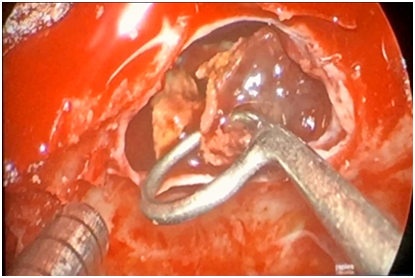

Three months later the patient presented acutely with complaints of headache, nausea/vomiting, altered mental status and diplopia. Physical examination revealed bitemporalhemianopsia and CNIII palsy. Laboratory and imaging workup revealed panhypopituitarism and a 1.7cmx1.9cm contrast enhancing surpasellar hemorrhagic mass impinging on the optic chiasm with extension into the cavernous sinuses R>L (Figure 2). Treatment options were discussed and the patient chose to undergo surgery for resection of the macroadenoma. The patient successively underwent Endoscopic Endonasal Transphenoid Resection of the Pituitary Adenoma (Insert surgical protocol) (Figure 3). Post-operatively, the patient had no major complications or focal motor or sensory neurological deficits. Patient noticed immediate improvement in his peripheral vision with marked resolution of CN III palsy several days post-op. Patient had no complications, clear rhinorrhea, or infection. Patient was placed on hormone replacement therapy (with Hydrocortisone, Synthroid and Vasopressin) due to his panhypopituitarism from pituitary apoplexy.

Figure 3 Intraoperative Photograph demonstrating the pituitary adenoma in the SellaTurcica prior to resection.